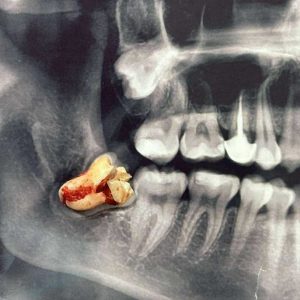

3D CBCT Imaging: We map your jaw with sub-millimeter accuracy to identify the ideal placement site.

| Wisdom Teeth Removal | Prevents crowding and infection. | Minimally invasive for a “painless” recovery. |